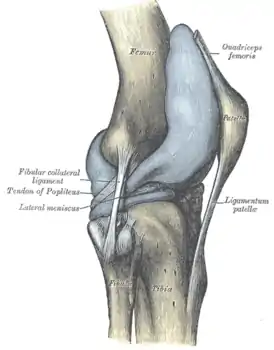

![]() Правый коленный сустав, сбоку. | |

В передней части сустава расположен надколенник (коленная чашечка). Надколенник и четырёхглавая мышца бедра соединены сухожилием, продолжением которого является связка надколенника. В связочный аппарат входят:

- боковые (малоберцовая и большеберцовая коллатеральные)

- задние (подколенная, дугообразная, связка надколенника, медиальная и латеральная поддерживающие)

- внутрисуставные (крестообразные, поперечная связка колена (между менисками)

Передний и латеральный вид колена.